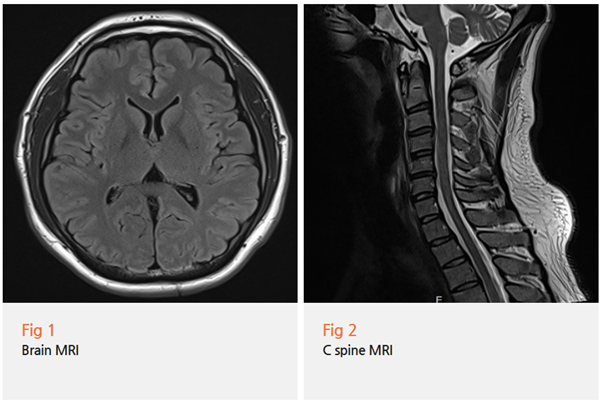

저는 일단 뇌 MRI부터 찍어보자고 제안했습니다.

환자분도 워낙 불안해하시고 계셨거든요.

뇌에 이상이 없다는 걸 확인해야 다음 단계로 넘어갈 수 있으니까요.

다행히 뇌 영상검사에서는 특이 소견이 없었어요.

하지만 저는 여기서 멈추지 않았어요.

두통 + 눈떨림의 조합,

그리고 1주일 이상 지속되는 증상...

뭔가 다른 원인이 있을 거라는 직감이 들더라고요.

그림16.png

그래서 경추 MRI를 추가로 촬영했습니다.

결과를 보는 순간 '아!' 했어요.

상부 경추에 기능장애가 명확하게 보이더라고요.